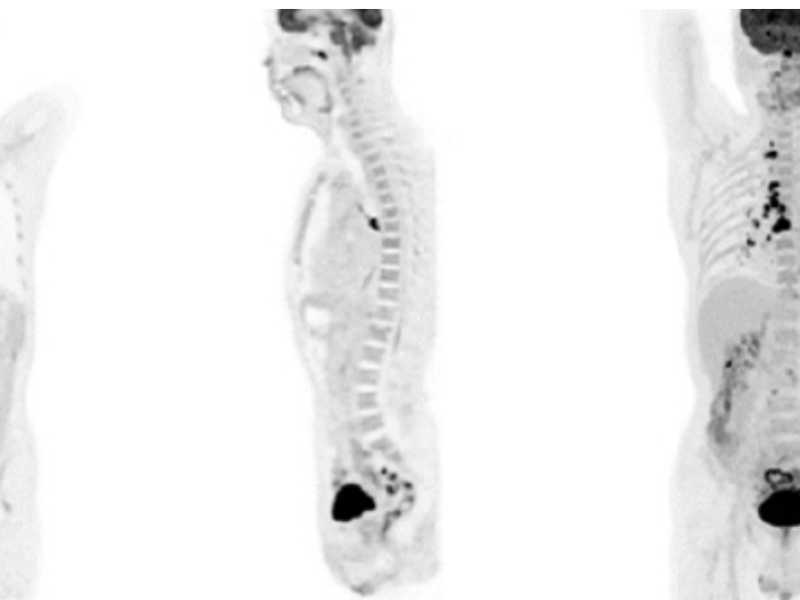

The large 24 cm axial digital PET field of view (FOV) provides exceptional image quality with 2.9 mm NEMA resolution that improves quantitative accuracy and small lesion detectability.

The uMI 550, born with AI, enables high-speed scanning without sacrificing image quality by combining the advanced AI iterative reconstruction engine trained with uEXPLORER® total-body PET data and a predictive AI-empowered workflow.

The Long axial 24 cm FOV and high system sensitivity enables whole-body scanning in 4 bed position within 8 minutes